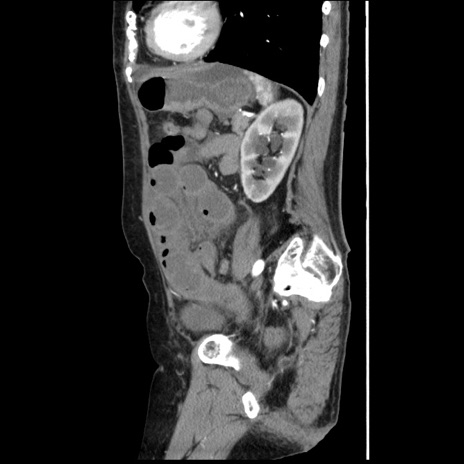

症例1(矢状断像)

【症例】80歳代女性

【主訴】腹痛

【現病歴】8時間前から腹痛あり来院。

【既往歴】糖尿病、脂質異常症、子宮体癌にて子宮全摘術

【身体所見】意識清明・会話良好だが腹痛で苦悶様、全腹部にわたって反跳痛と圧痛あり

【データ】WBC 13600、CRP 0.14、LDH 224、CK 90